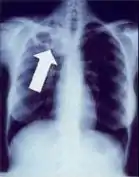

In active pulmonary TB, infiltrates or consolidations and/or cavities are often seen in the upper lungs with or without mediastinal or hilar lymphadenopathy or pleural effusions ( tuberculous pleurisy). However, lesions may appear anywhere in the lungs. In disseminated TB a pattern of many tiny nodules throughout the lung fields is common - the so-called miliary TB. In HIV and other immunosuppressed persons, any abnormality may indicate TB or the chest X-ray may even appear entirely normal.

Abnormalities on chest radiographs may be suggestive of, but are not necessarily diagnostic of, TB. However, chest radiographs may be used to rule out the possibility of pulmonary TB in a person who has a positive reaction to the tuberculin skin test and no symptoms of the disease.

Cavitation or consolidation of the apexes of the upper lobes of the lung or the tree-in-bud sign[8] may be visible on an affected patient's chest X-ray.[1] The tree-in-bud sign may appear on the chest CTs of some patients affected by tuberculosis, but it is not specific to tuberculosis.[8]